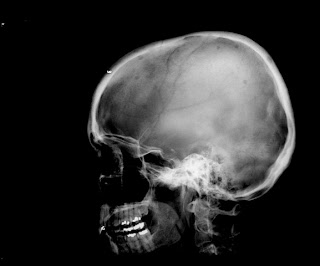

The skull image shows multiple round, punched-out lytic areas. A prominent lytic lesion is noted in the left femur on the next image and one in the right ischium on the third. The fourth image shows a small lesion in the posteriorlateral 5th rib. Note the lack of sclerotic margin.